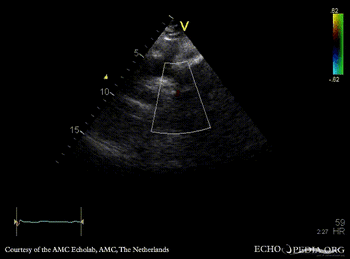

| Suprasternal view, Color Doppler in a patient with coarctatio aortae | Continuous-wave doppler: high velocity flow in descending aorta, sawtooth phenomenon |